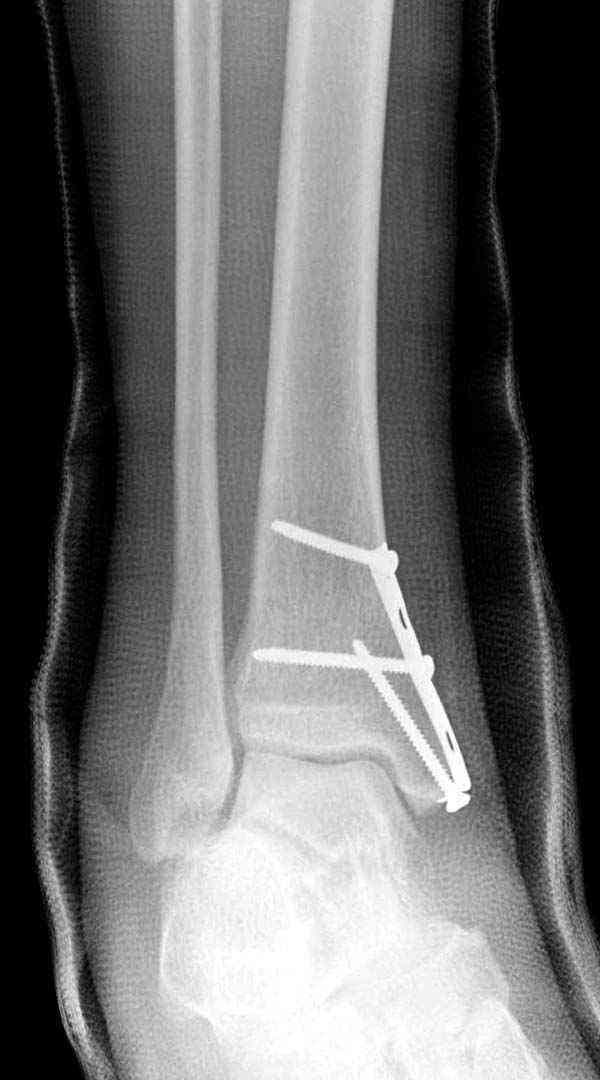

Описанная вами техника "Внутренняя лодыжка фиксирована по Веберу, наружная реконструктивной пластиной с наложением болта-стяжки" существует, но этот подход морально устарел, и применяется очень редко, только при отсутствии имплантов.

Реконструкционные пластины на лодыжке очень грубые, и из-за тонкого слоя кожи над дистальным концом малоберцовой могут осложниться пролежнями кожи изнутри.

Нет первичных снимков, перелом очень низкий и под большим сомнением диагноз разрыва синдесмоза. Медиальная сторона отрепонирована на "хорошо" и, по-видимому, прорезание проволоки произошло во время операции. Без снимков трудно судить о высоте малоберцовой, а лодыжка находится в варусе. Лагирование получилось, но возле тонких шурупов передне-задний шуруп выглядит немного тяжеловато.

Во всех руководствах АО имеется описание техники применения низкопрофильных пластин 1/3 трубки, которые могут быть применены для фиксации наружной лодыжки. Фиксацию проводят кортикальными 3.5 мм шурупами, и если дистальная фиксация недостаточная, тогда усиливают конструкцию созданием hook plate. Сгибая конец пластины на последнем отверстии, внедряют его в дистальный отдел, и тем самым создается дополнительная фиксация.

Современные преконтурированные пластины не имеют таких недостатков, и разделяются на правые и левые, а также на латеральные и задние. Множественные дистальные шурупы 2.7 мм уменьшают подкожное раздражение, и такой имплант можно оставить на долгий срок без удаления.

Для молодых достаточным бывает обычная лодыжечная пластина без блокировки, и только у пожилых с остеопорозом лучше взять полиаксиальные пластины с угловой стабильностью.

Здесь несколько частных случаев: перелом голеностопа со сравнительными снимками и разрыв синдесмоза, а также медиальная Hook пластина.